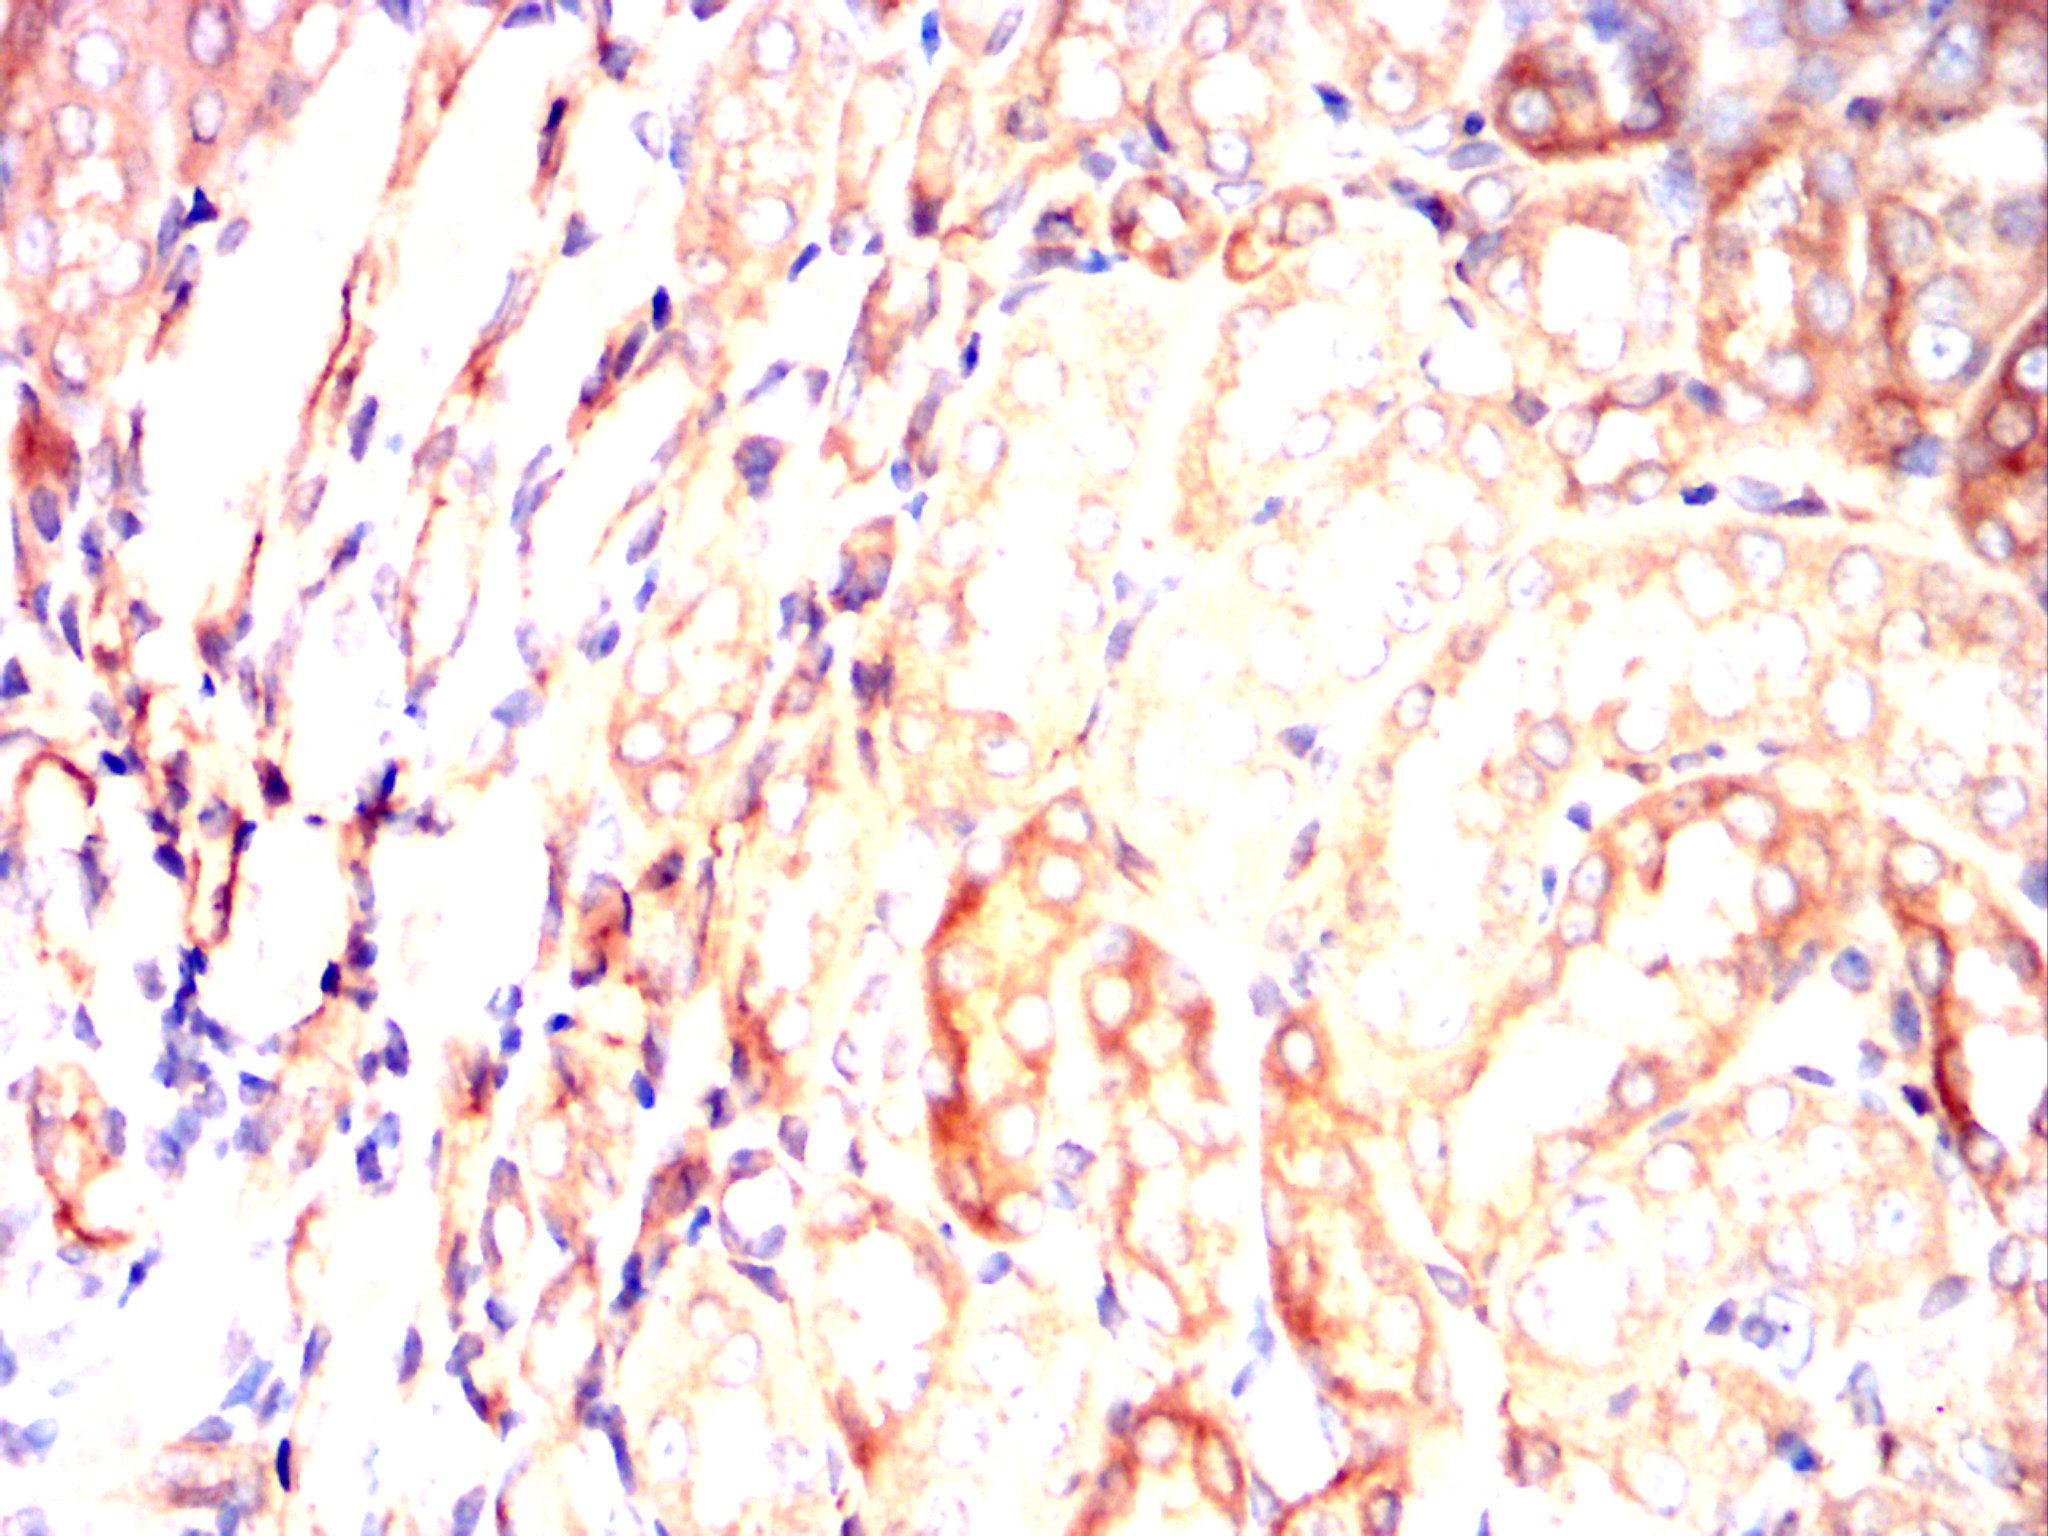

Immunohistochemical analysis of paraffin-embedded human lung cancer tissues using SERPINE1 mouse mAb with DAB staining.

Immunohistochemical analysis of paraffin-embedded human kidney cancer tissues using SERPINE1 mouse mAb with DAB staining.

Immunohistochemical analysis of paraffin-embedded Rat kidney using SERPINE1 mouse mAb with DAB staining.

Immunohistochemical analysis of paraffin-embedded Rabbit kidney using SERPINE1 mouse mAb with DAB staining.